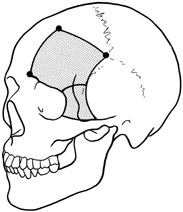

Procedure

The transcranial orbitotomy uses a frontal craniotomy with removal of a portion of the orbital roof to expose the orbital apex or superior orbit. This is best performed by a neurosurgeon familiar with skull-base surgical approaches. In most cases, the supraorbital rim over the involved side is removed en bloc with the frontal bone flap (Fig. 13). The anterior one-half or two-thirds of the orbital roof breaks free with removal of the rim and frontal bone flap, and the remaining posterior portion of the roof can be removed with rongeurs. Historically, it was suggested that all orbital tumors be removed via craniotomy, because before the imaging era it was difficult to anticipate the intraorbital location of a mass.18 The transfrontal approach was first described by Jones10 in 1970. Jane and colleagues19 proposed the current technique in 1982. Refinements have been discussed by Maroon and Kennerdell9 and Housepian.20 This operation has been termed the panoramic orbitotomy by Rootman21 because of the wide area of exposure offered by this procedure.

Fig. 13. Schematic diagram for transcranial orbitotomy in which the supraorbital rim is removed en bloc with the frontal bone flap. This provides extensive exposure to the superior and lateral orbit.